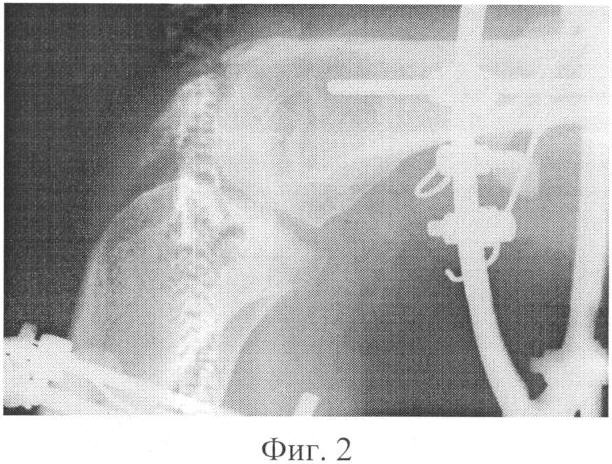

фиг.2 – рентгенограмма коленного сустава больной в процессе фиксации аппаратом;

В послеоперационном периоде, начиная с 5 дня, в течение 30 дней производили дозированную разработку движений в оперированном суставе с постепенно увеличивающейся амплитудой в диапазоне сгибания-разгибания (фиг.2). На 38 день после операции аппарат был демонтирован. В дальнейшем больная прошла курс ЛФК и физиотерапевтического лечения.